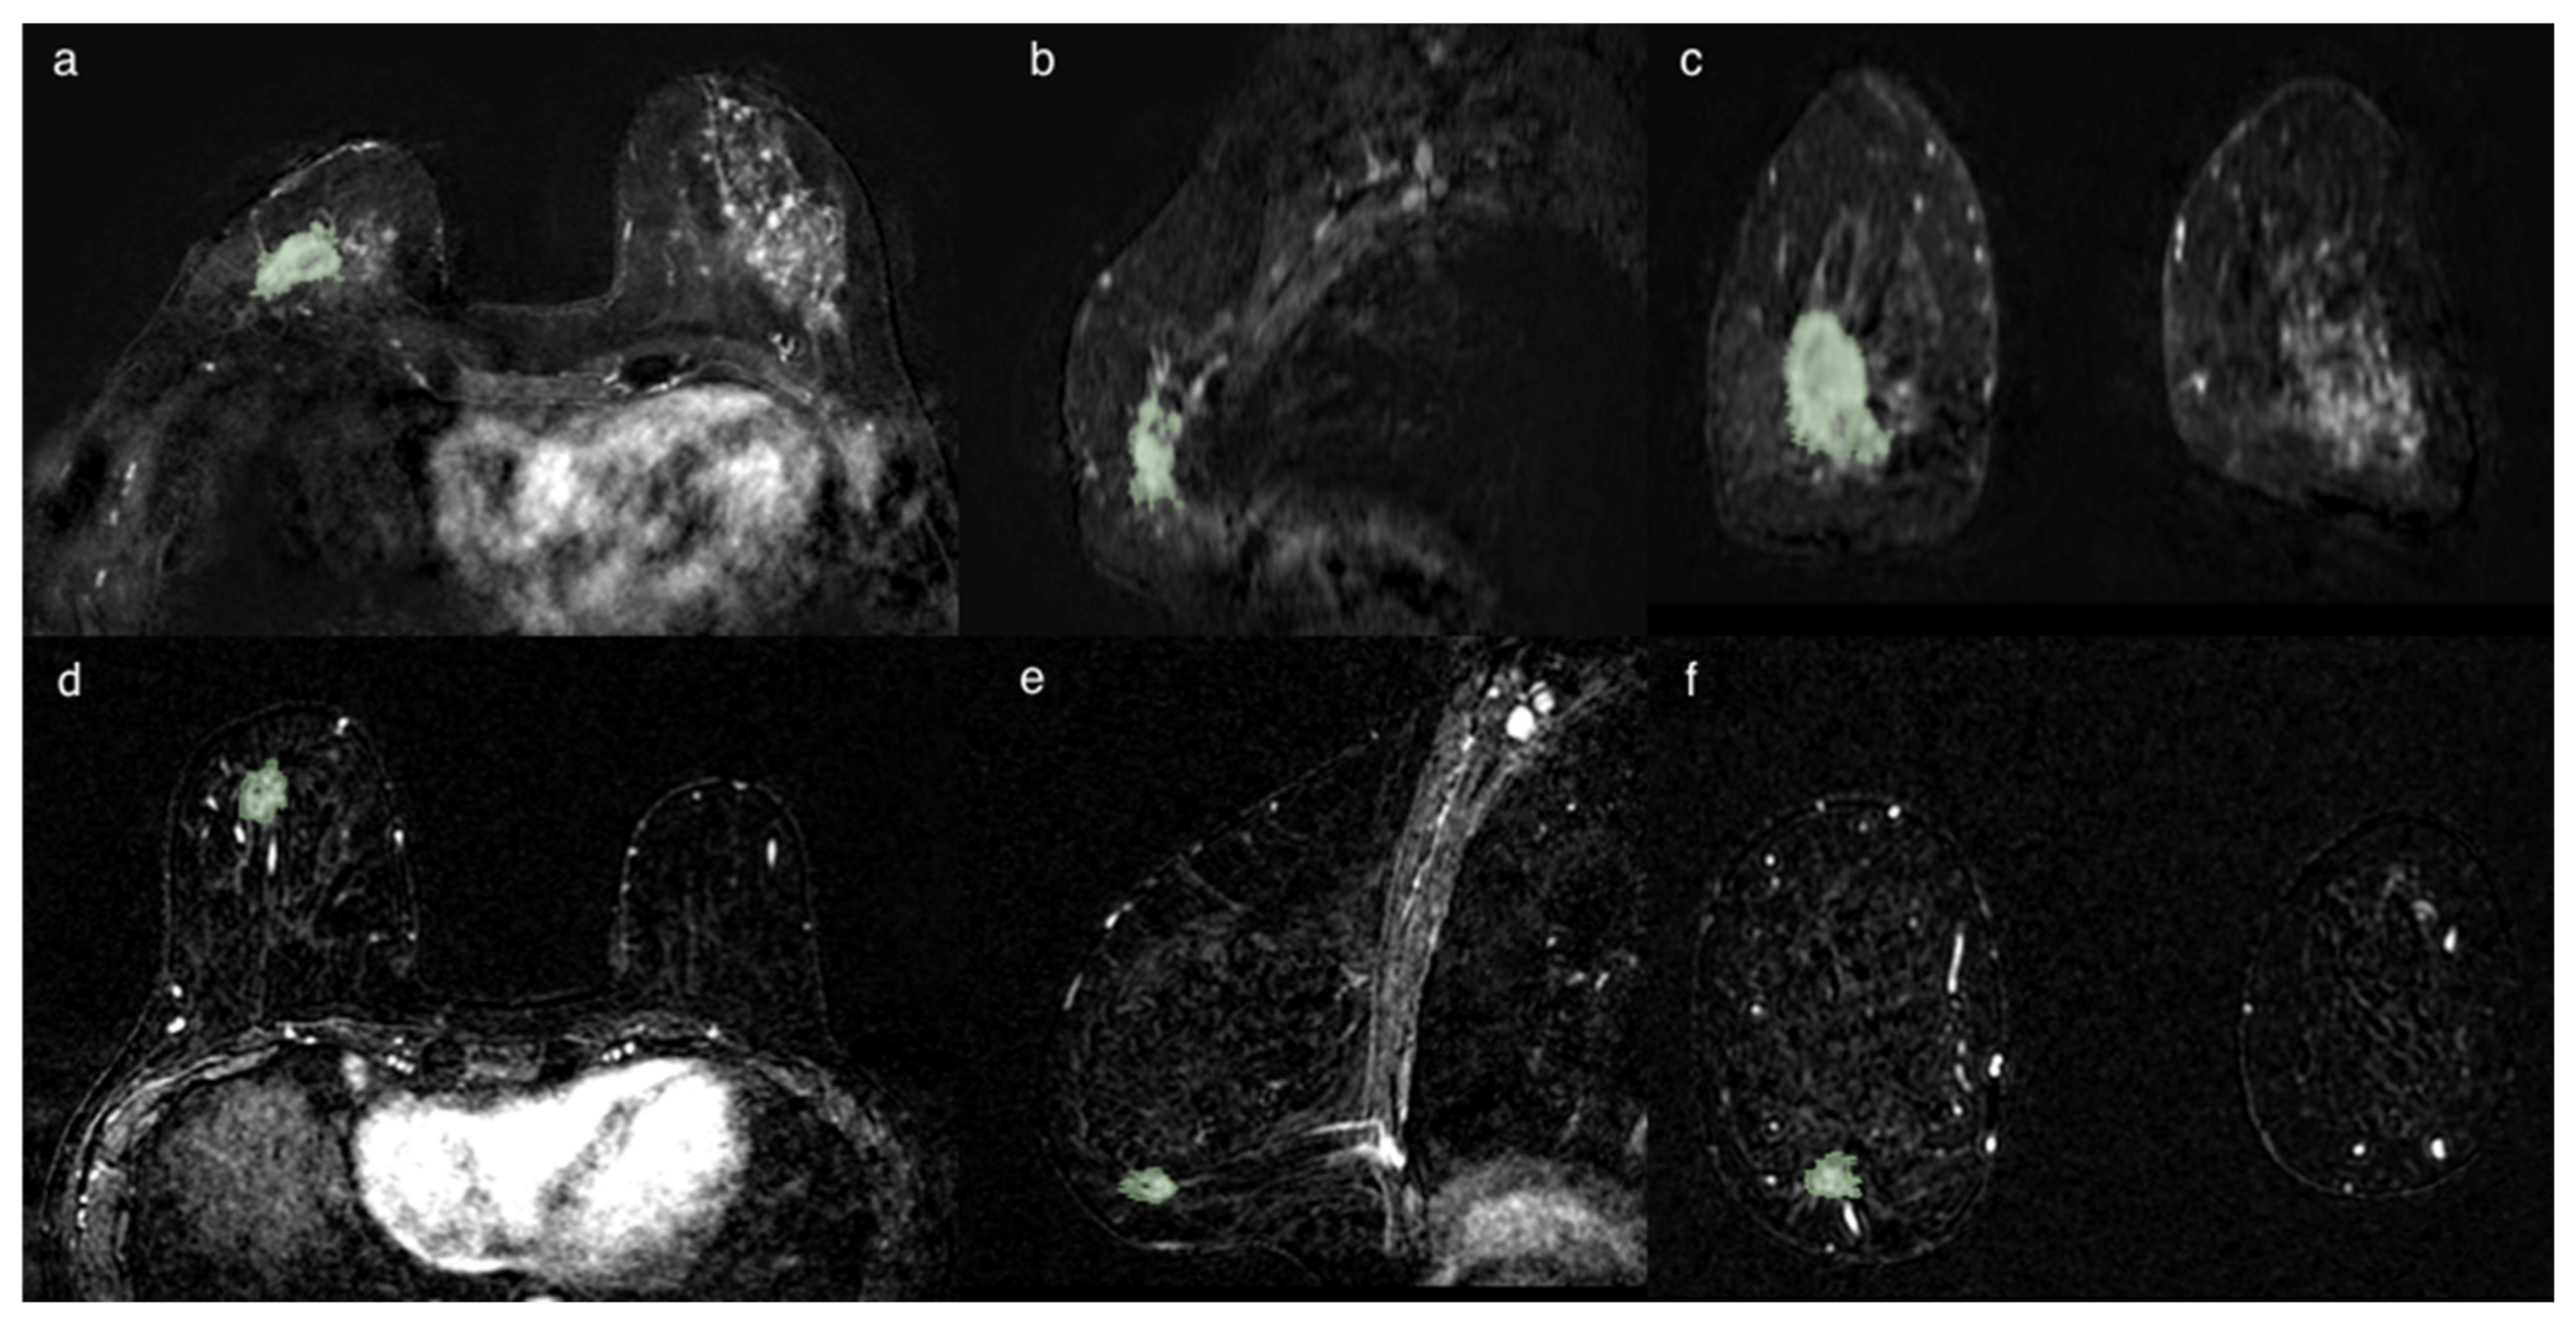

Figure 6. Example of applicability of the proposed approach. Two cases of invasive breast cancer, characterized by very similar MRI features (morphology, margin, post-contrast intensity, IS/T curve, and size and position of the two lesions are comparable) as shown in the left panels. The first case (first row) is a ductal G3 LUMINAL A carcinoma, in 31yo patient with familiarity, the second one (second row) is also a ductal G2 LUMINAL A carcinoma, but in 68yo patient without familiarity. Despite the common MRI and histological features, the produced classifier correctly categorizes the two patients as positive and negative LN status, respectively.

An example of how the classifier correctly works is reported in the two cases shown in Figure 6.